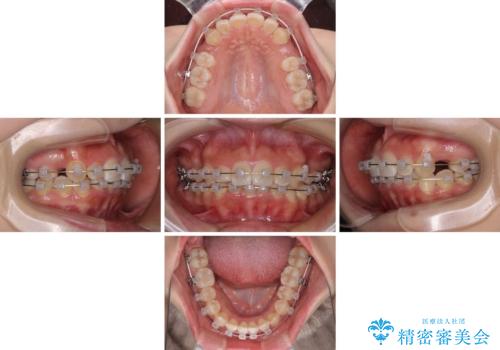

- クリアブラケット

- 1年10ヶ月

- 10-30回